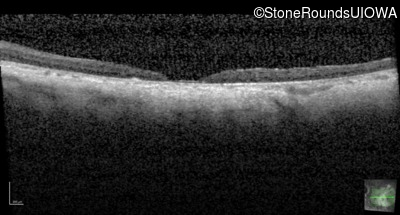

Optical Coherence Tomography - Right - 10/200 sc

Exemplar / OCT Stack

OCT Stack